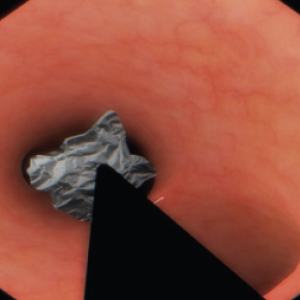

Real-feel surgical simulation. Diagnostic and surgical skills in Endoscopy

EndoVision sets the standard in simulation for hands-on-training in endoscopic procedures. Allowing trainees realistic and safe clinical experiences

EndoVision offers exposure to an extensive library of modules and patient cases to challenge diagnostic and psychomotor skills in preparation for real presentations.